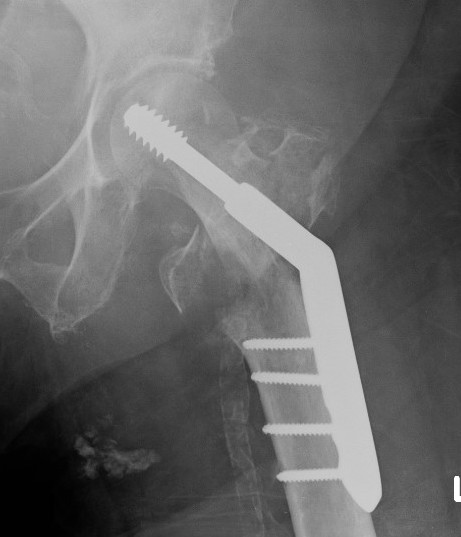

Dynamic hip screw

Mechanism

Plate is a lateral tension band whilst the sliding screw allows controlled fracture impaction

Technique

- traction table with anatomic reduction

- traction, adduction, internal rotation

Lateral approach to femur

- elevate vastus lateralis and control bleeding from perforators

Guide wire

- centred in femoral head in 2 planes

- tip-apex distance < 25 mm

Tip - apex distance

- from tip of screw to apex femoral head

- accumulative on AP and lateral

- > 25 mm, increases cut out

Measure angle

- wire in centre of neck / centre of head

- usually 130o prosthesis

Ream to within 5 mm of end of wire

- tap

- insert screw / tip apex distance < 25 mm

- attach plate